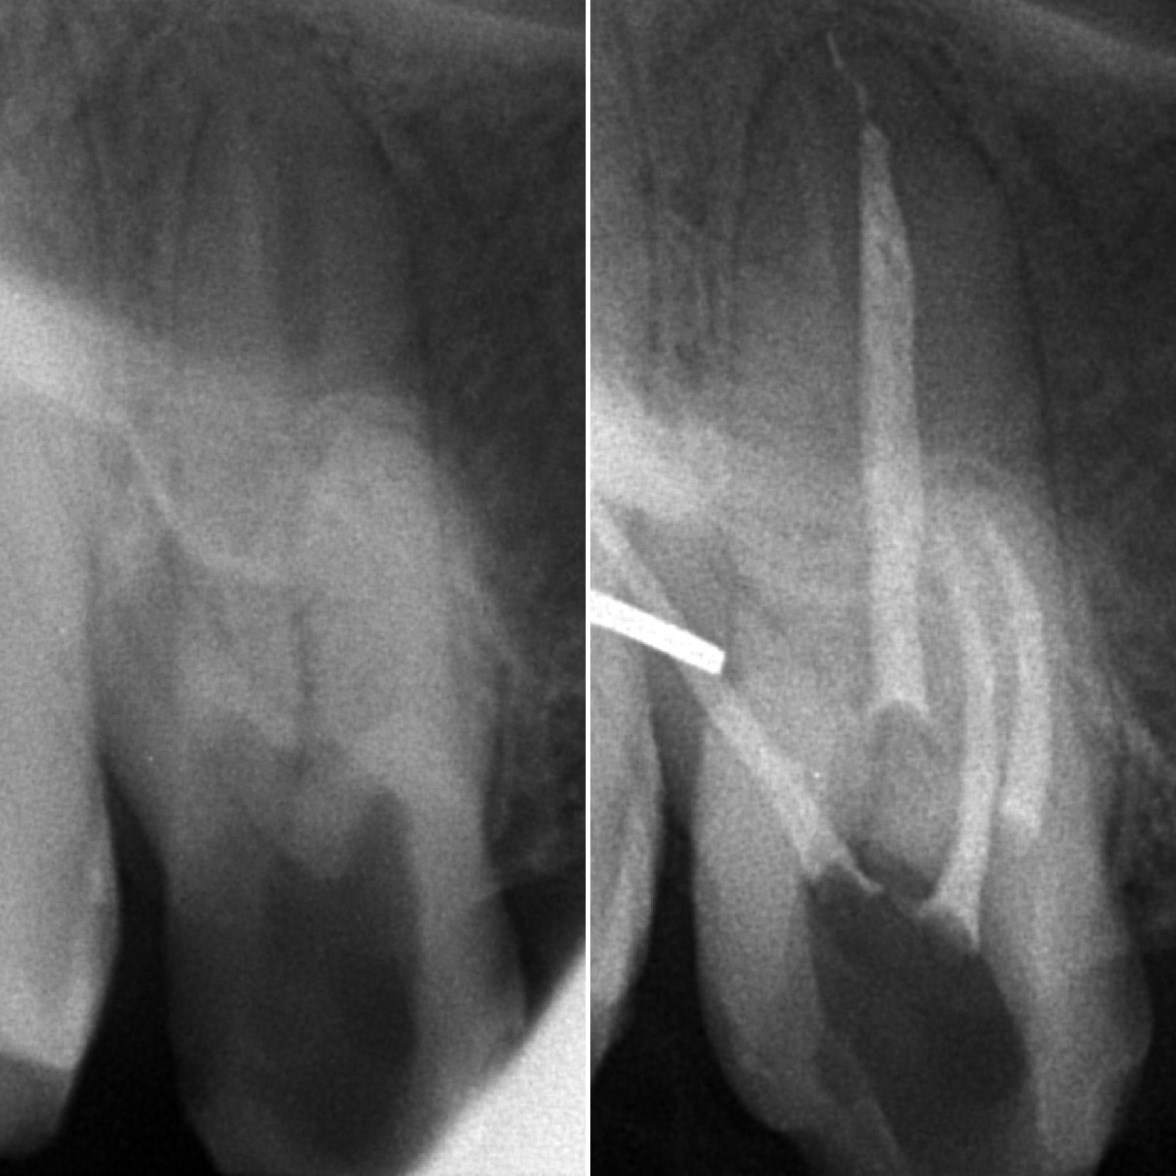

• Диагностика и лечение кариеса и его осложнений (пульпиты, периодонтиты)

• Эндодонтическое лечение корневых каналов с использованием стоматологического микроскопа

2022 год – «Первичная эндодонтия с использованием современных клинических протоколов» Андрей Кольба

2023 год – «Первичная эндодонтия» Виталий Весна